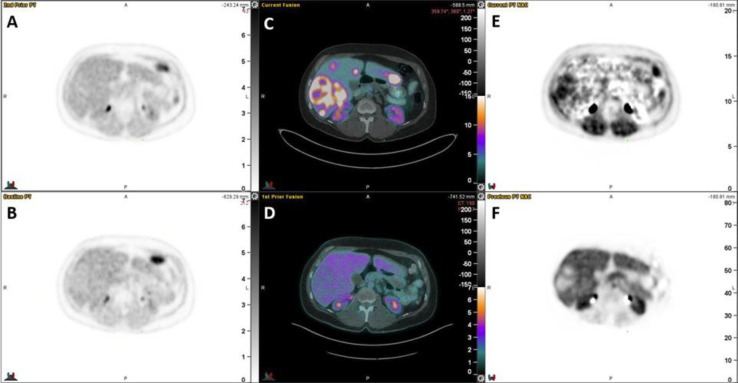

Results: Ten patients were enrolled with primary sites including pancreas (n=3), small bowel (n=3), rectum (n=2), duodenum (n=1) and lung (n=1). Six subjects were scored 1, three subjects were scored 2, and one subject was scored 3. All lesions evaluated were located in the liver. Quantitative [18F]FMISO parametric imaging showed evidence of increased uptake rate (Ki) in the photopenic areas of the DONUT lesions in 8/10 subjects. Surrounding uptake rate in normal liver was extremely low. In the qualitative delayed image assessment, only one subject demonstrated [18F]FMISO uptake greater than surrounding normal liver (small bowel primary, G2).

Conclusion: Only one of ten patients with DONUT lesions demonstrated increased [18F]FMISO uptake rate on delayed static imaging. In contrast, dynamic imaging demonstrated increased [18F]FMISO uptake rate in the region of [68Ga]DOTATATE photopenia on 8 of 10 patients. Future research using [18F]FMISO in NEN patients should incorporate dynamic imaging.